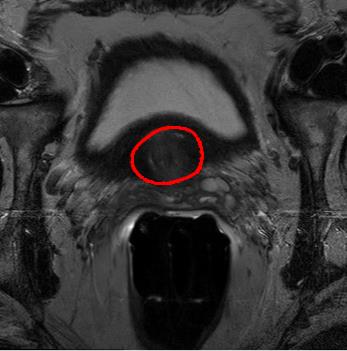

We trained our network on 77 patients. The input images and the manual ground truth annotation are shown in Fig.4. As we have described above, these images were acquired from different patients, and these images include the clinical variability. To evaluate our method, we randomly selected 4 patients with 64 images before training. These images do not take part in training and the prostate has been manually pre-delineated by a radiologist, which were used as the ground truth to evaluate the performance of automatic segmentation. We also selected dice coefficient as the evaluation method[30]. And to validate our method against U-Net and fully convolutional networks (FCNs), we used the same dataset to train and test the U-Net and FCNs.

To intuitively compare the proposed method with U-Net and FCN, the segmentation results of some representative and challenging samples are shown in Fig 5. It can be seen that these prostate images have fuzzy boundaries and the pixel intensity distributions are inhomogeneous both inside and outside of the prostate. Besides, both prostate and nonprostate regions have similar contrast and intensity distributions. All of these phenomenons make the segmentation difficult.

As shown in the second column in Fig 5. FCN model failed to obtain satisfactory result, though the model could detect part of prostate. However, for the details of prostate, for instance, the boundaries, the network can not assign the label to each pixel accurately.

In U-Net model, the label has be assigned to each pixel and has improved the segment accurate as shown in the third column in Fig 5. However, the network always make a mistake when assigning the label to nonprostate regions. Besides, for the boundaries information, the network cannot work well. At last, the segmentation results lose some important information and there still exist some errors.

The results of deeply supervised CNN are shown in the fourth column of Fig 5. The fuzzy boundaries are well detected by our proposed method. Besides, the segmentation boundary are more continuous and smooth than the competing method. It can be proved that additional supervised layers are useful for the texture and boundaries of prostate.